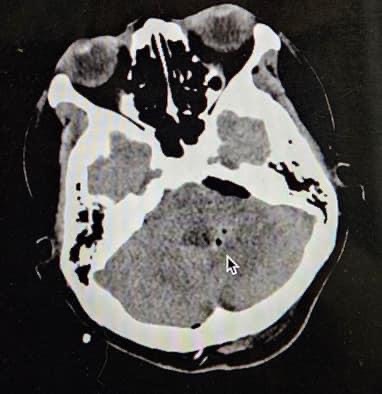

Trong đó, có 2 bệnh nhân ghi nhận lúc vào bệnh viện đã trong tình trạng hôn mê, kích thích, vã mồ hôi, mạch hơn 100 lần/phút, huyết áp không xác định được, có vết thương vị trí vùng tim trước ngực trái. Siêu âm tổng quát tại giường có dịch màng ngoài tim lượng trung bình. Tiên lượng ban đầu rất nặng, nguy cơ tử vong cao. Trường hợp còn lại tiên lượng nhẹ hơn. Ngay khi tiếp nhận, đội ngũ bác sĩ trực của Khoa Ngoại Lồng ngực, Khoa Cấp cứu, Khoa Chẩn đoán hình ảnh, Khoa Phẫu thuật - Gây mê hồi sức nhanh chóng tiến hành hội chẩn và quyết định phẫu thuật cấp cứu ngay cho các bệnh nhân. Sau khi mở ngực, phẫu thuật viên nhanh chóng kiểm tra, tìm được lỗ thủng ở tim, và tiến hành khâu cầm máu. Các ca phẫu thuật đều kéo dài từ 2 - 3 giờ đồng hồ. Sau phẫu thuật, bệnh nhân được đưa về Phòng Hồi sức ngoại để hồi sức và theo dõi giai đoạn hậu phẫu.

| Thực hiện ca phẫu thuật cấp cứu khâu vết thương tim cho bệnh nhân |